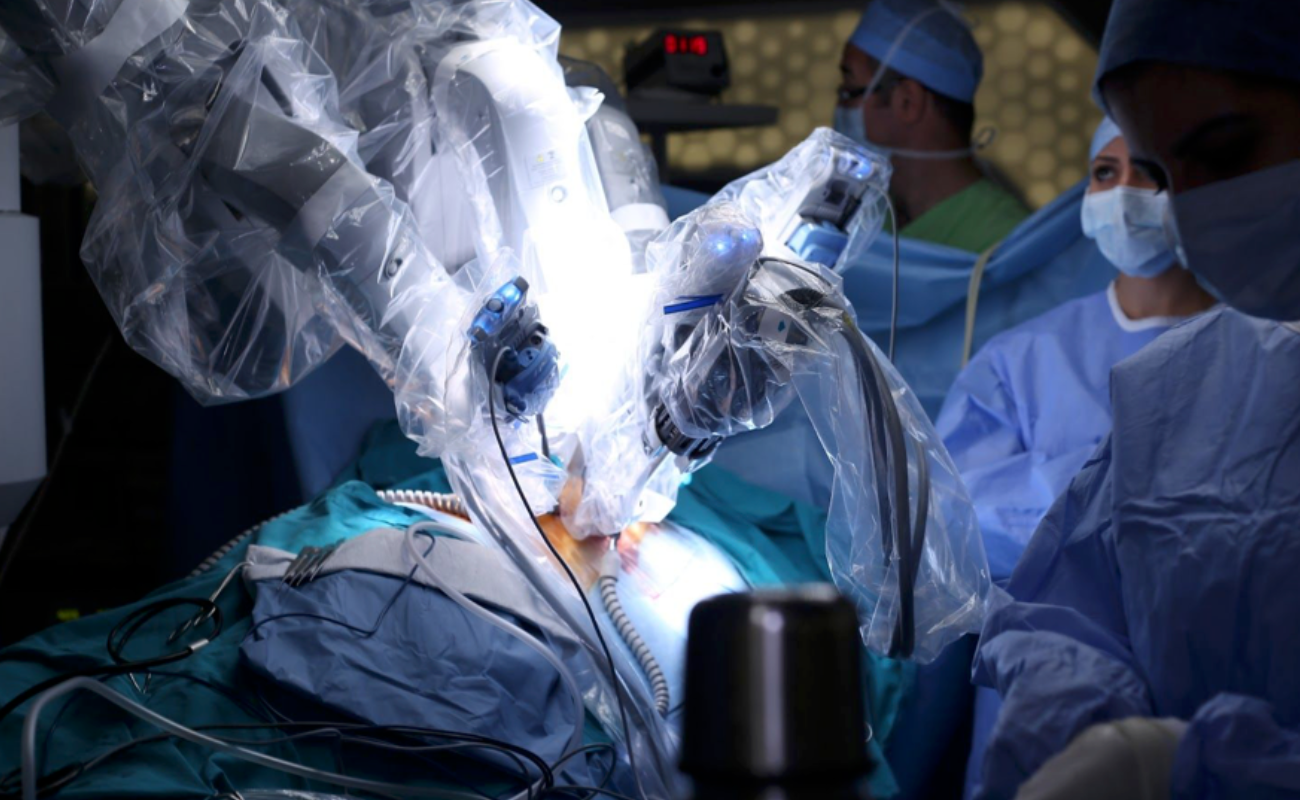

With state-of-the-art robotic joint replacement surgery offering greater accuracy, smaller incisions, and faster recovery times.

Robotic Surgery: The Future of Healthcare in Chennai

Robotic surgery is revolutionizing healthcare, particularly in Chennai, where advanced medical techniques are becoming increasingly accessible

Robotic Surgery in Chennai: A Guide for Patients and Caregivers

Robotic surgery is transforming modern healthcare, offering precision, minimally invasive techniques, and faster recovery for patients. As one of the most significant advancements in surgical technology,

Modern Technology Makes Robotic Surgery Safer Than Ever

In the world of surgery, one technology that has made waves since its introduction is robotic surgery. It has swiftly moved from novelty to necessity in the medical world. Robotic surgery has changed every surgeon’s